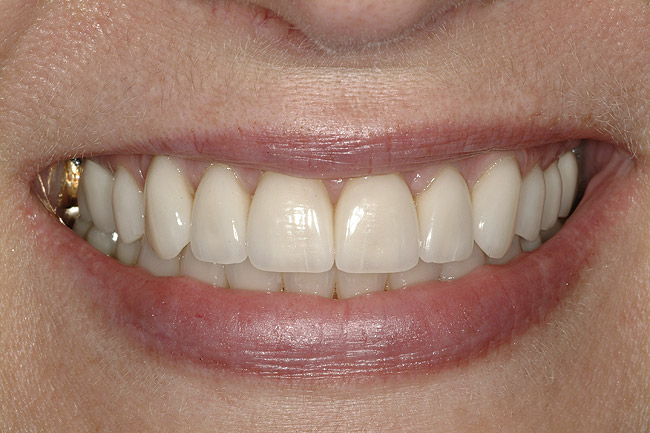

O pacientă în vârstă de 44 de ani s-a prezentat pentru evaluarea şi îmbunătăţirea zâmbetului ei. Acuza principală era reprezentată de afişarea neatractivă a coroanelor posterioare din aur, asociată cu petele albe inestetice de pe dinţii frontali (fig. 1, 2). Scopul ei convingător pentru solicitarea tratamentului a fost acela de a dobândi un „zâmbet deosebit”.

DENTO-FACIAL: Evaluarea zâmbetului pacientei a evidenţiat o dinamică labială maxilară medie şi afişarea ţesuturilor la zâmbire (fig. 2). Nivelurile gingivale maxilare inegale, exostoza osoasă vestibulară vizibilă corespunzător 1.6., dinţii rotaţi sau malpoziţionaţi, coloraţia de pe mai mulţi dinţi frontali, o „linie a surâsului inversată” , asimetria dentară şi un plan ocluzal maxilar neregulat reprezentau puncte semnificative în cadrul evaluării dentofaciale. Dorinţa pacientei de a avea un zâmbet ideal sau „generat de media” a accentuat dificultatea cazului. Dinamica labială maxilară medie şi afişarea în consecinţă a ţesuturilor a dictat evaluarea riscului pentru acest caz.